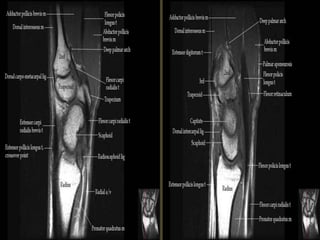

Wrist X-ray Anatomy.

Pronator quadratus.